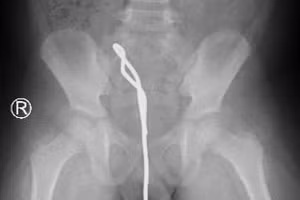

Bắt chước trong phim, bé trai 6 tuổi nhét thanh sắt nửa mét vào người 06/01/2022 12:09 GD&TĐ - Bắt chước phim, bé trai vào nhà vệ sinh và nhét thanh sắt thông cống vào hậu môn. Bệnh nhi được đưa vào Bệnh viện Nhi đồng Thành phố (Thành phố Hồ Chí Minh) cấp cứu khẩn.